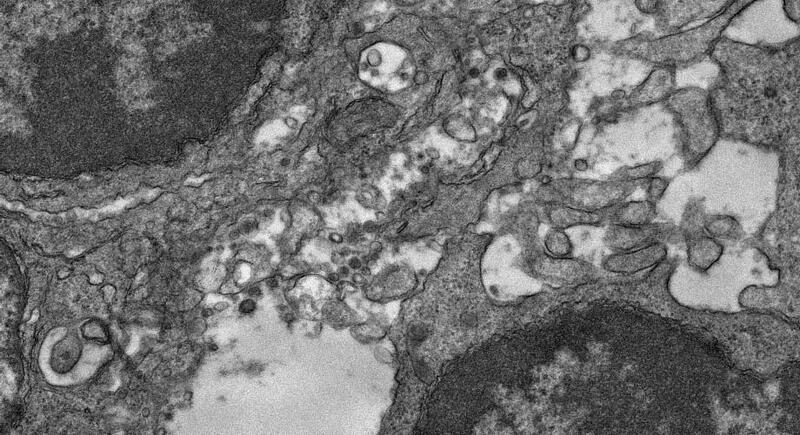

Estudios publicados anteriormente mostraron que los pacientes que necesitan tratamiento hospitalario debido a la COVID-19 recién diagnosticada tienen un metabolismo de la glucosa reducido en el cerebro, lo que se asocia con el deterioro de la función cognitiva. Para evaluar si los pacientes que sufren COVID de larga duración experimentan déficits similares, los investigadores realizaron pruebas neuropsicológicas e imágenes PET de 18F-FDG cerebrales.

Se recomendó la realización de imágenes PET con 18F-FDG a todos los pacientes que recibieron asesoramiento, y 14 de los 31 pacientes procedieron a ello. La evaluación clínica del escáner de cada paciente no reveló hallazgos patológicos distintos ni diagnósticos alternativos. Cuando se compararon las exploraciones con las de un grupo de control, no se observaron diferencias significativas.